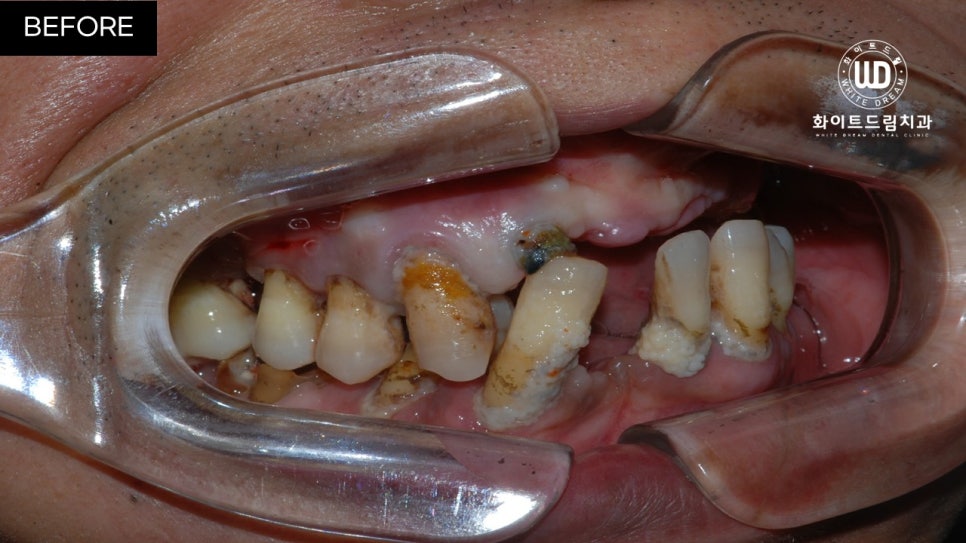

오늘 말씀드릴 환자분은 이전 케이스들과는 달리 보존된 치아는 많지만 전체적으로 흔들리는 등 상태가 좋지 않아 내원하셨다고 합니다.

해당 환자분은 전체발치 / 40대임플란트 / 전체임플란트식립 환자분이었습니다.

임플란트 식립 전 상, 하악 모습입니다.

육안으로 보이실지 모르겠으나 잔존한 치아 주위염이 심한 상태셨는데요. 뿐만 아니라 치아 파절과 함께 영구치의 뿌리 대부분이 손상되어 있는 상태였습니다.

이미 발치되어 있는 쪽은 치아가 소실된지 오랜 시간이 지나 잇몸뼈가 부족한 상태였고, 현 상태로는 픽스쳐를 식립할 수 없어 전체 발치 후 상악 양측 구치부 상악동 거상술 및 전체 치조골 이식을 동반한 전체 임플란트 식립을 진행하기로 했습니다.